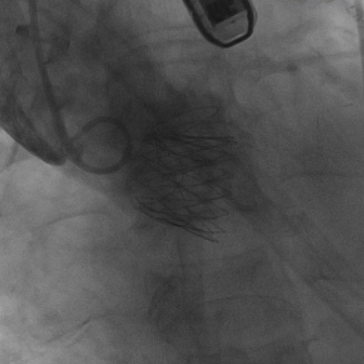

图3.术前24号球囊预扩